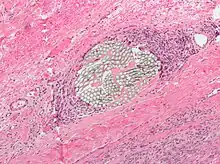

Micrograph of a H&E stained tissue section showing a non-absorbable multi-filament surgical suture with a surrounding foreign-body giant cell reaction

Suture material is often broken down into absorbable thread versus non-absorbable thread, which is further delineated into synthetic fibers versus natural fibers. Another important distinction among suture material is whether it is monofilament or polyfilament (braided) [2]